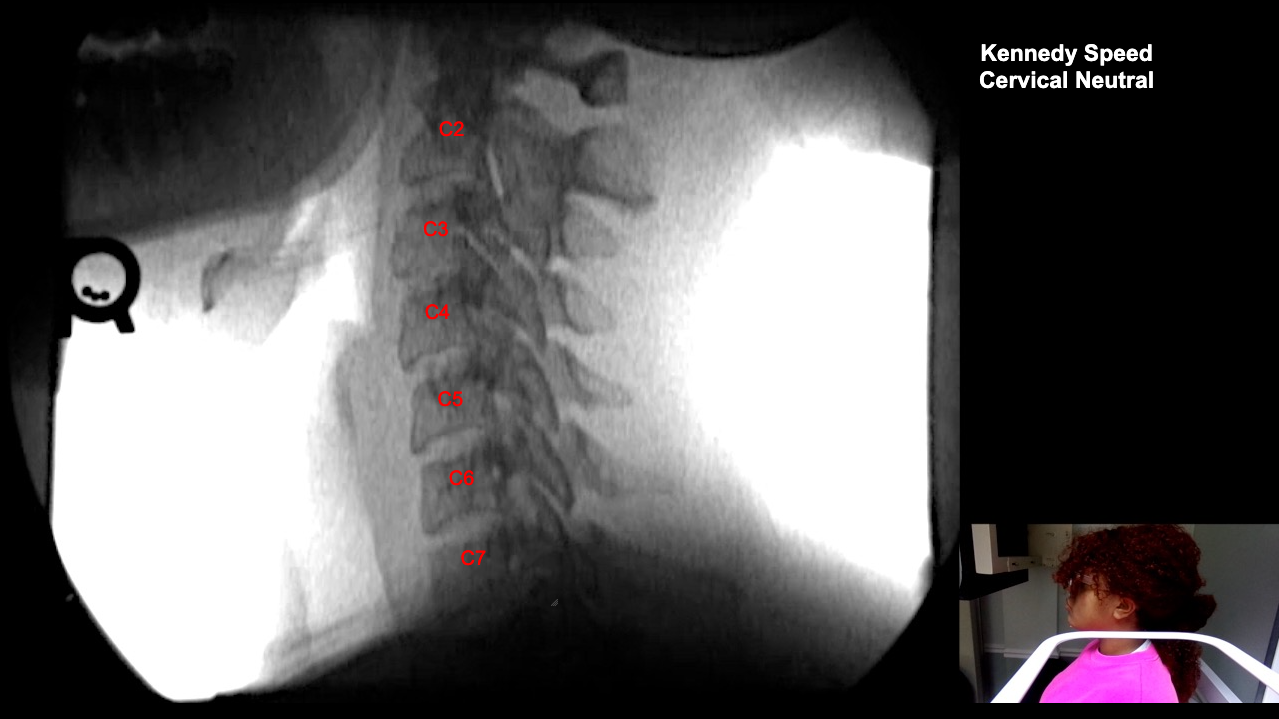

Image 2